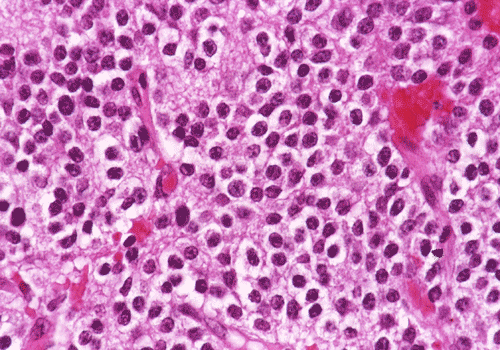

Panel A and B are low-magnification photomicrographs featuring solid sheets of isomorphous, small round to ovoid neoplastic cells with a delicate but rich vascular network. There are also intervening irregular patches of fibrillary neuropils. At high-magnification, the tumor cells appear as fairly uniform round to polygonal cells with perinuclear halo (Panel C). An island of neuropil is present in Panel D. The tumor cells are immunoreactive for synaptophysin (Panel E). The tumor cells were not immunoreactive for neurofilament proteins. At the ultrastructural level, the neoplastic cells contain numerous cell processes filled with vessicles and dense core granules (Panel F and G). Dense core granules and vescicles in high-mangification are shown in Panel H. The vesicles have structures similar to that of the synaptic vesicles, a feature of neuronal differentiation.

Histological, the tumor is composed of solid sheets of small, round to polygonal, isomorphic tumor cells with distinct cell membrane. Within the neoplastic cells is a delicate vascular network. Microcalcifications, when present, are distributed throughout the tumor. The cytoplasm is fine and amphophilic. Perinuclear halo is usually present and prominent, leading to an impression of a clear cell tumor. The summation of these features generates a “honey-comb” pattern similar to that of oligodendroglioma and clear cell ependymoma. The nuclei of neurocytoma are round, small, and contain fine and speckled chromatin. Nucleoli are indistinct. Mitotic figures are not readily seen or infrequent. Irregular and small islands of neuropils are present. Perivascular arrangement of neuropils in some areas may closely mimic the coronary perivascular fibrillary hypocellular mantles (perivascular pseudorosettes) that are considered evidence of ependymoma. The real ependymal pseudorosettes are more orderly and fibrillary. A high index of suspicion is important to avoid this trap.